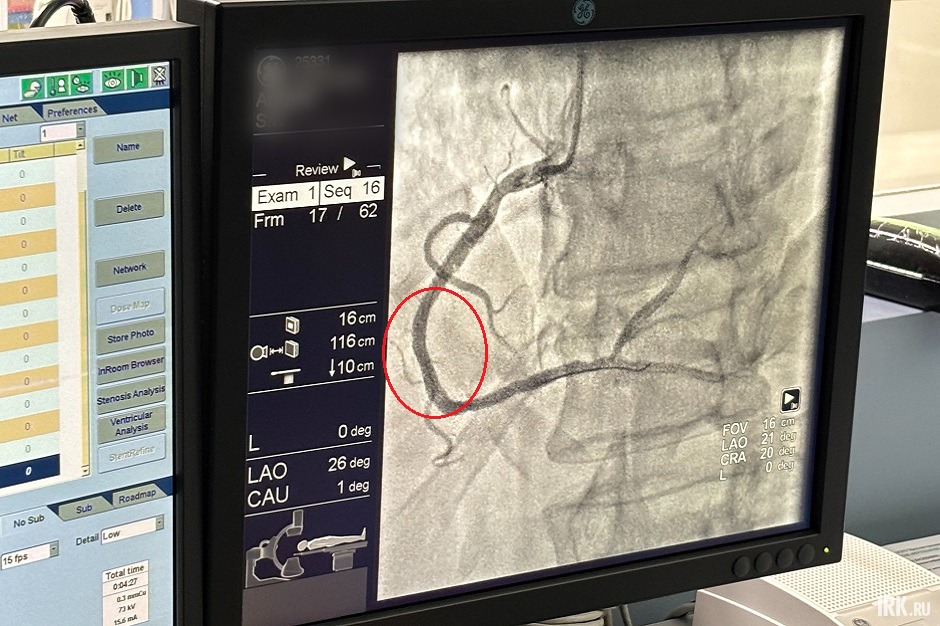

— Пациента с инфарктом буквально в течение нескольких минут из приемного отделения доставляют в рентген-операционную, где пунктируется лучевая артерия, далее через нее вводится катетер, который позволяет просмотреть бассейны сердца и оценить наличие стенозов либо спазмов коронарных артерий, — пояснила Евгения Чуйко. — Это помогает нам в ранние сроки визуализировать место инфаркта и уже селективно провести операцию: в то место, где наблюдается стеноз или окклюзия — сужение просвета сосуда или его закупорка — вводим стент и восстанавливаем кровоток.

Когда у человека диагностируют инфаркт, первый час после случившегося самый важный, доктора называют его «золотой час». Это время, в течение которого врачи проводят диагностику бассейнов сердца, проверяют проходимость сосудов, наличие в них бляшек. Процедура занимает 10-15 минут, затем начинают устанавливать стент. Как правило, если нет осложнений, то вся операция длится 25-30 минут.

Сегодня на операционном столе — 67-летний мужчина, поступивший в приемное отделение с инфарктом. Ранее ему проводили коронарографию. Тогда было установлено, что бляшка в правой коронарной артерии занимала 50%. Такой показатель врачи считают гемодинамически незначимым, то есть поражение сосуда минимальное и не вызывает очевидных нарушений кровотока. В таком случает лечение еще не требуется, но следует постоянно наблюдаться у специалистов. Однако сейчас у мужчины появились боли в сердце, и медики приняли решение повторно провести коронарографию, во время которой выяснилось, что просвет в артерии стал еще уже и теперь больному уже необходимо стентирование.